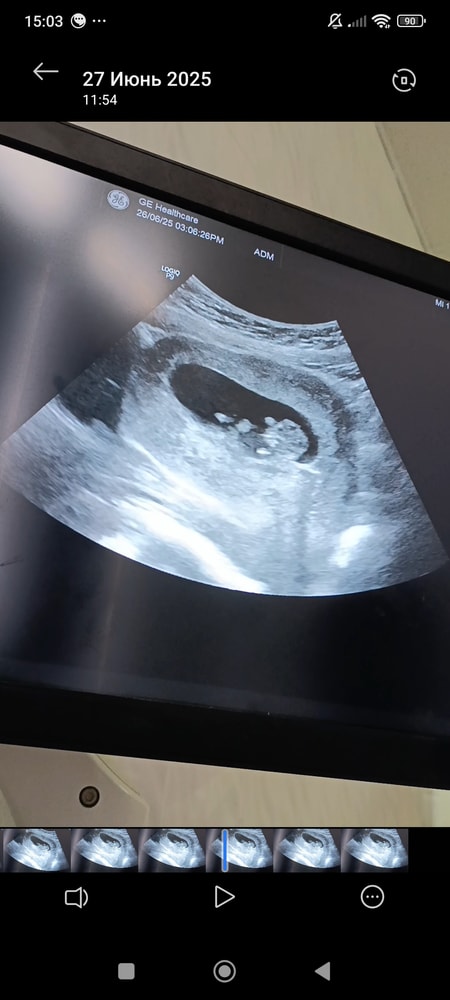

УЗИ, КТГ, доплерПересматриваю видео с вчерашнего узи уже не знаю какой раз 😁 Срок 10.1 вчера был,по узи 10.3.Что за чудесный человечек,хотя без 'стакана' и не поймёшь что где 🤣 Желаю всем кто ждет этого в скором времени увидеть своё маленькое чудо ❤️

Да вроде все понятно, головка, ручки, ножки!!!! Легкой беременности!

Мама Лиля, Ну нам то без сомнений понятно имея столько детей 😁 я и глаз вижу))Вам тоже лёгкой беременности 😊